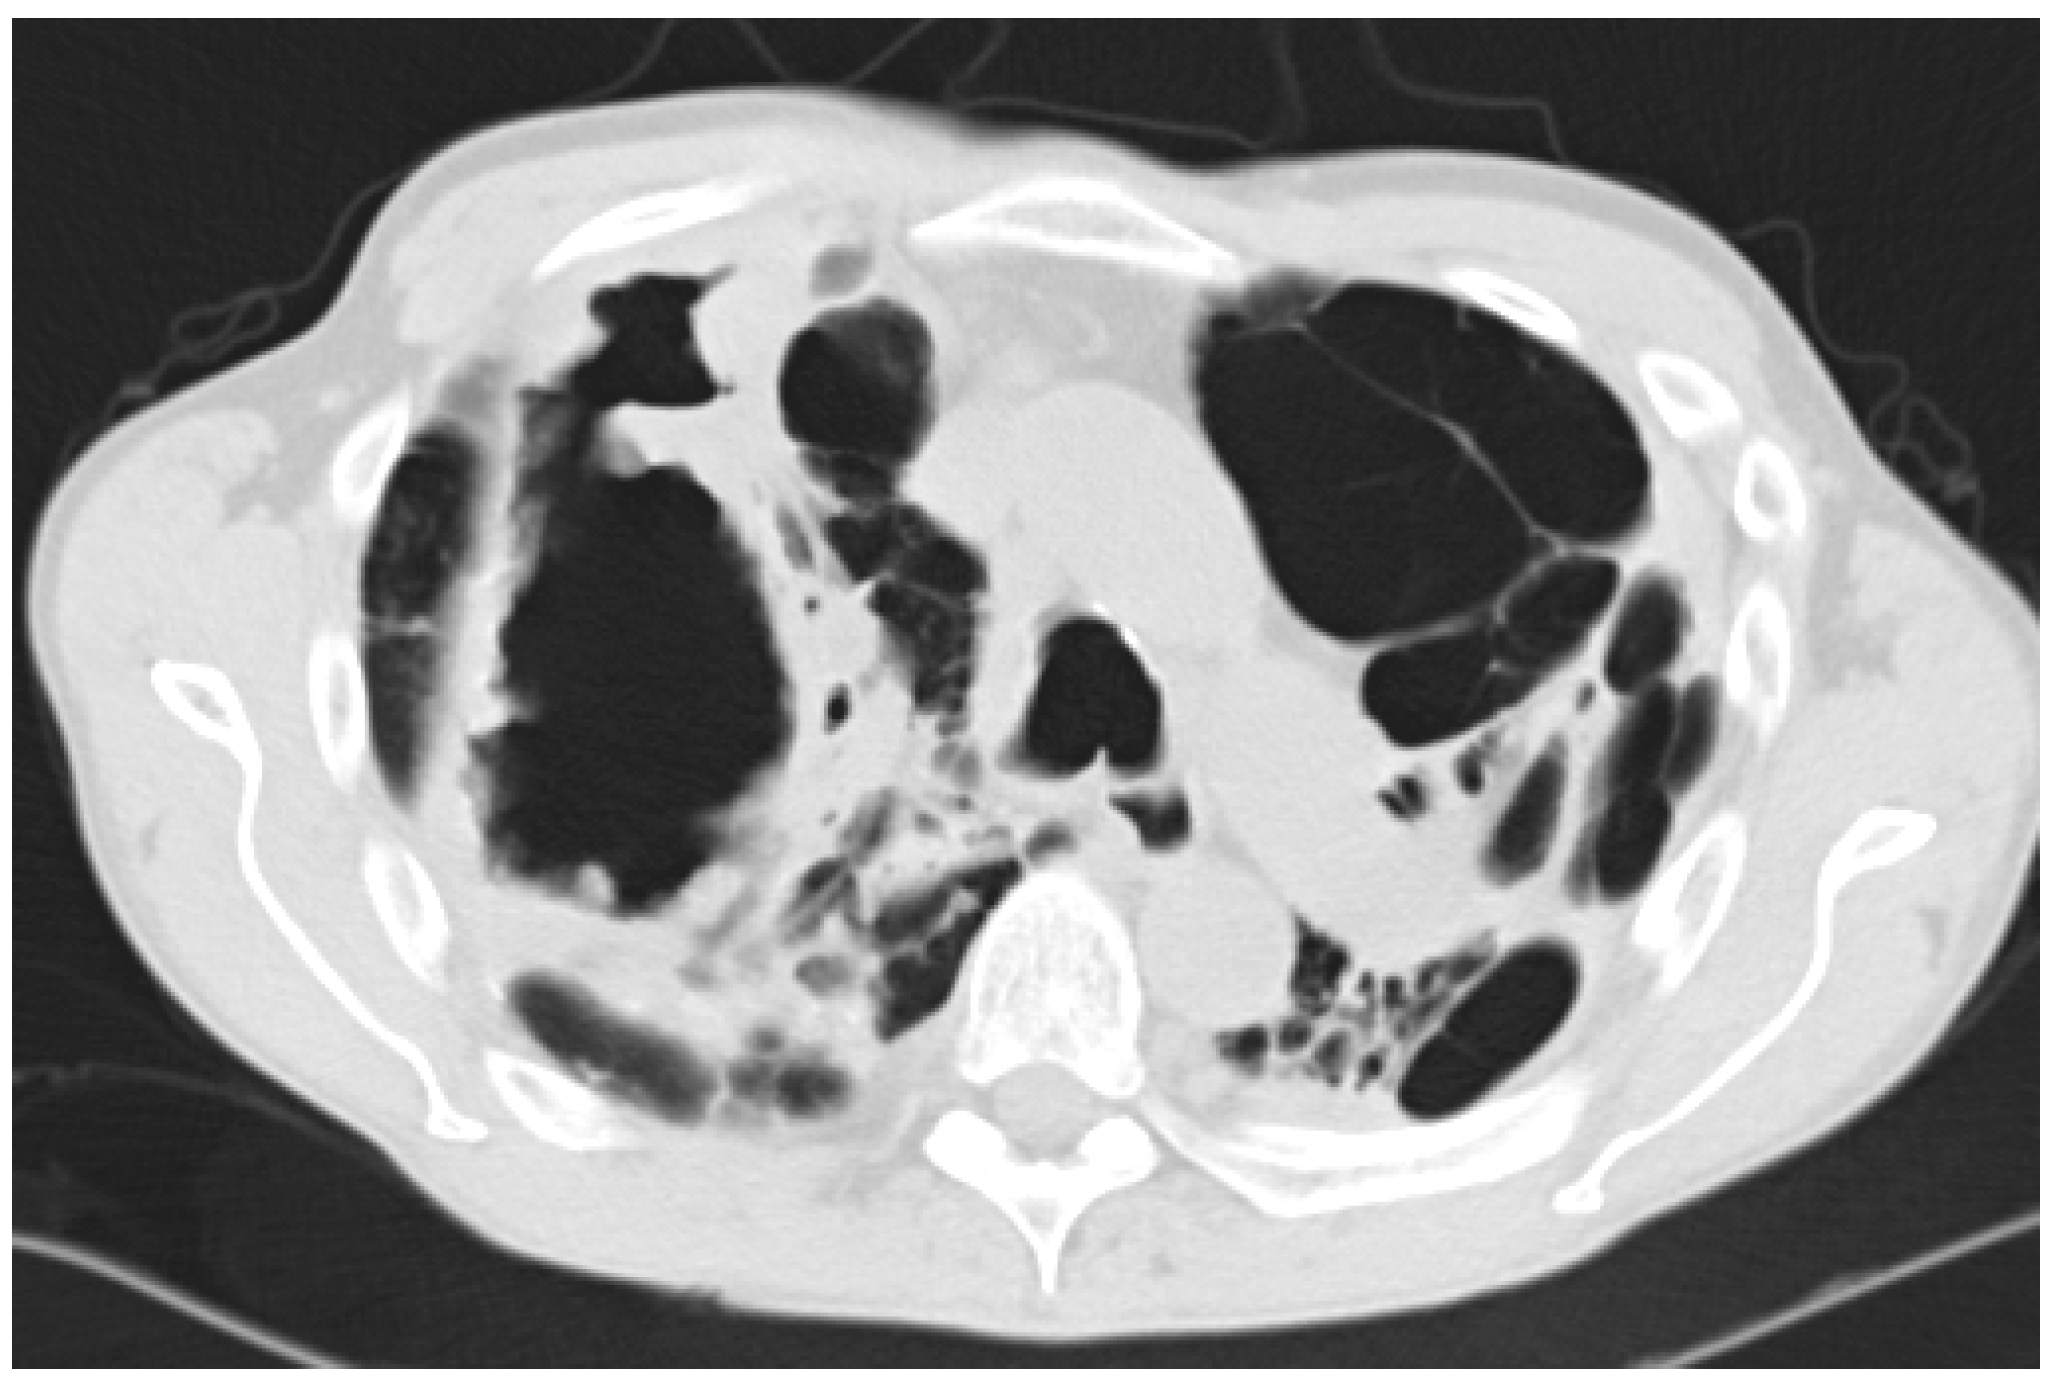

4.2. Radiology

- Desai, S.R.; Hedayati, V.; Patel, K.; Hansell, D.M. Chronic aspergillosis of the lungs: Unravelling the terminology and radiology. Eur. Radiol. 2015, 25, 3100–3107. [Google Scholar] [CrossRef] [PubMed]

- Franquet, T.; Muller, N.L.; Gimenez, A.; Guembe, P.; de La Torre, J.; Bague, S. Spectrum of pulmonary aspergillosis: Histologic, clinical, and radiologic findings. Radiographics 2001, 21, 825–837. [Google Scholar] [CrossRef] [PubMed]

- Greene, R. The radiological spectrum of pulmonary aspergillosis. Med. Mycol. 2005, 43, S147–S154. [Google Scholar] [CrossRef] [PubMed]